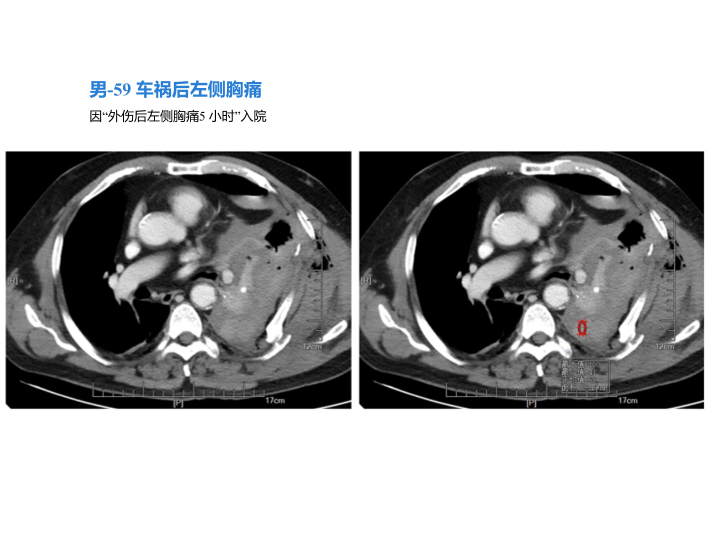

胸部外伤及胸腔积液处理